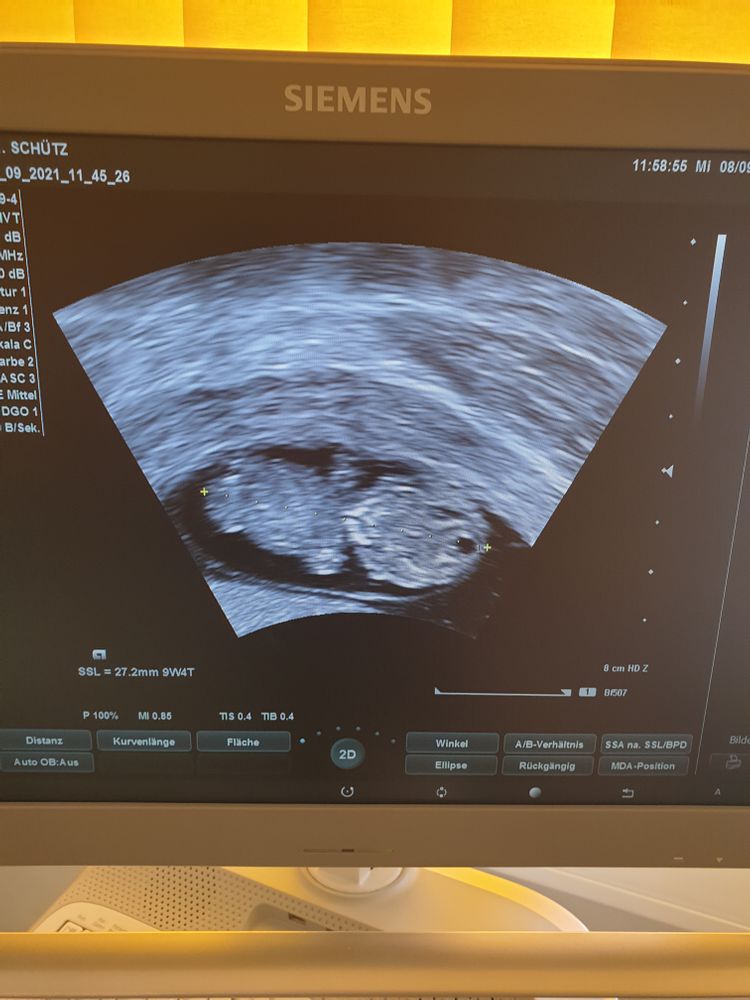

УЗИ на 10ой неделе

В среду была на УЗИ, наконец встала на учет.

Срок ПДР немного сдвинулся, комп показал, что у меня 9.4 недели. Отталкиваясь от подсчёта машины, дата родов 9, а не 12 апреля.

Изображение

Все нужные за